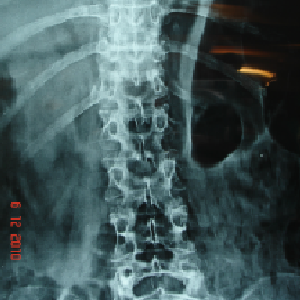

Double cord syndrome – DIASTOMATOMYELIA – is a very rare entity, wherein patient

is having congenital deformity of spine with separation of the spinal cord into

two halves by a bony or fibrous septum It is a great challenge to operate these

pts as , if something goes wrong, pt would become paraplegic for her life time.

Perticularly, in this case, as pt was only 9 years old and having congenital deformity

of the vertebrae, it was corrected simultaneously at Sola civil hospital - ahmedabad.